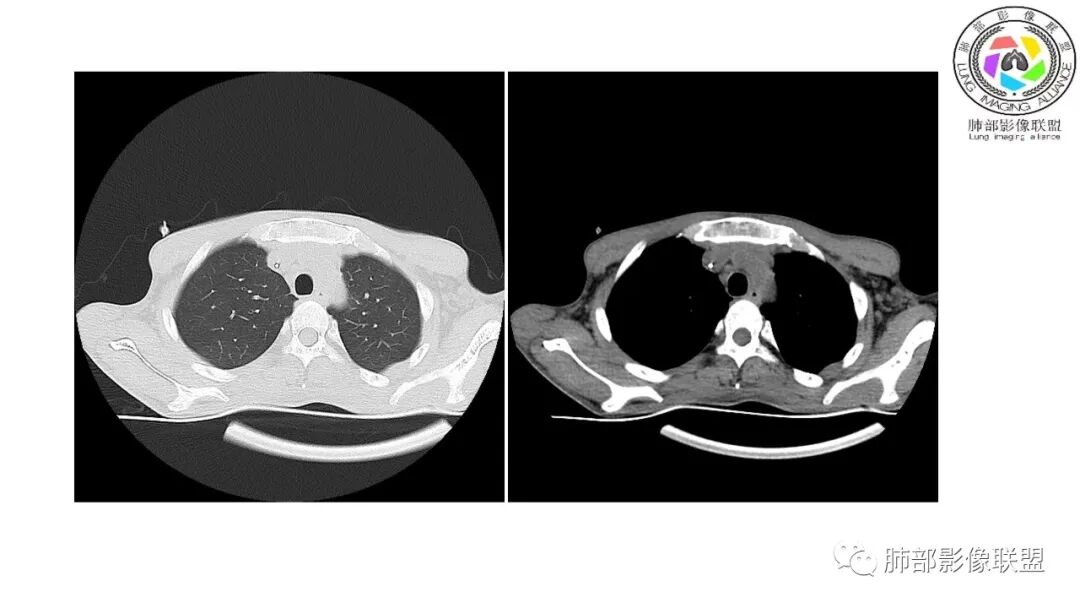

影像与临床:1.青年男性,HlV阳性,颜面部皮疹(未提供皮疹图像)、发热(高热),实验室CRP、PCT高,T-Spot阴性。2.右肺下叶空洞结节,壁厚不均,边界清楚,其内线状影,未见液平及钙化,未见卫星灶,纵隔淋巴结增大,双侧腋窝见增大淋巴结。心腔内低密度提示贫血可能。肝脾影增大,未见结节影及块影。腹膜后见多发增大淋巴结。